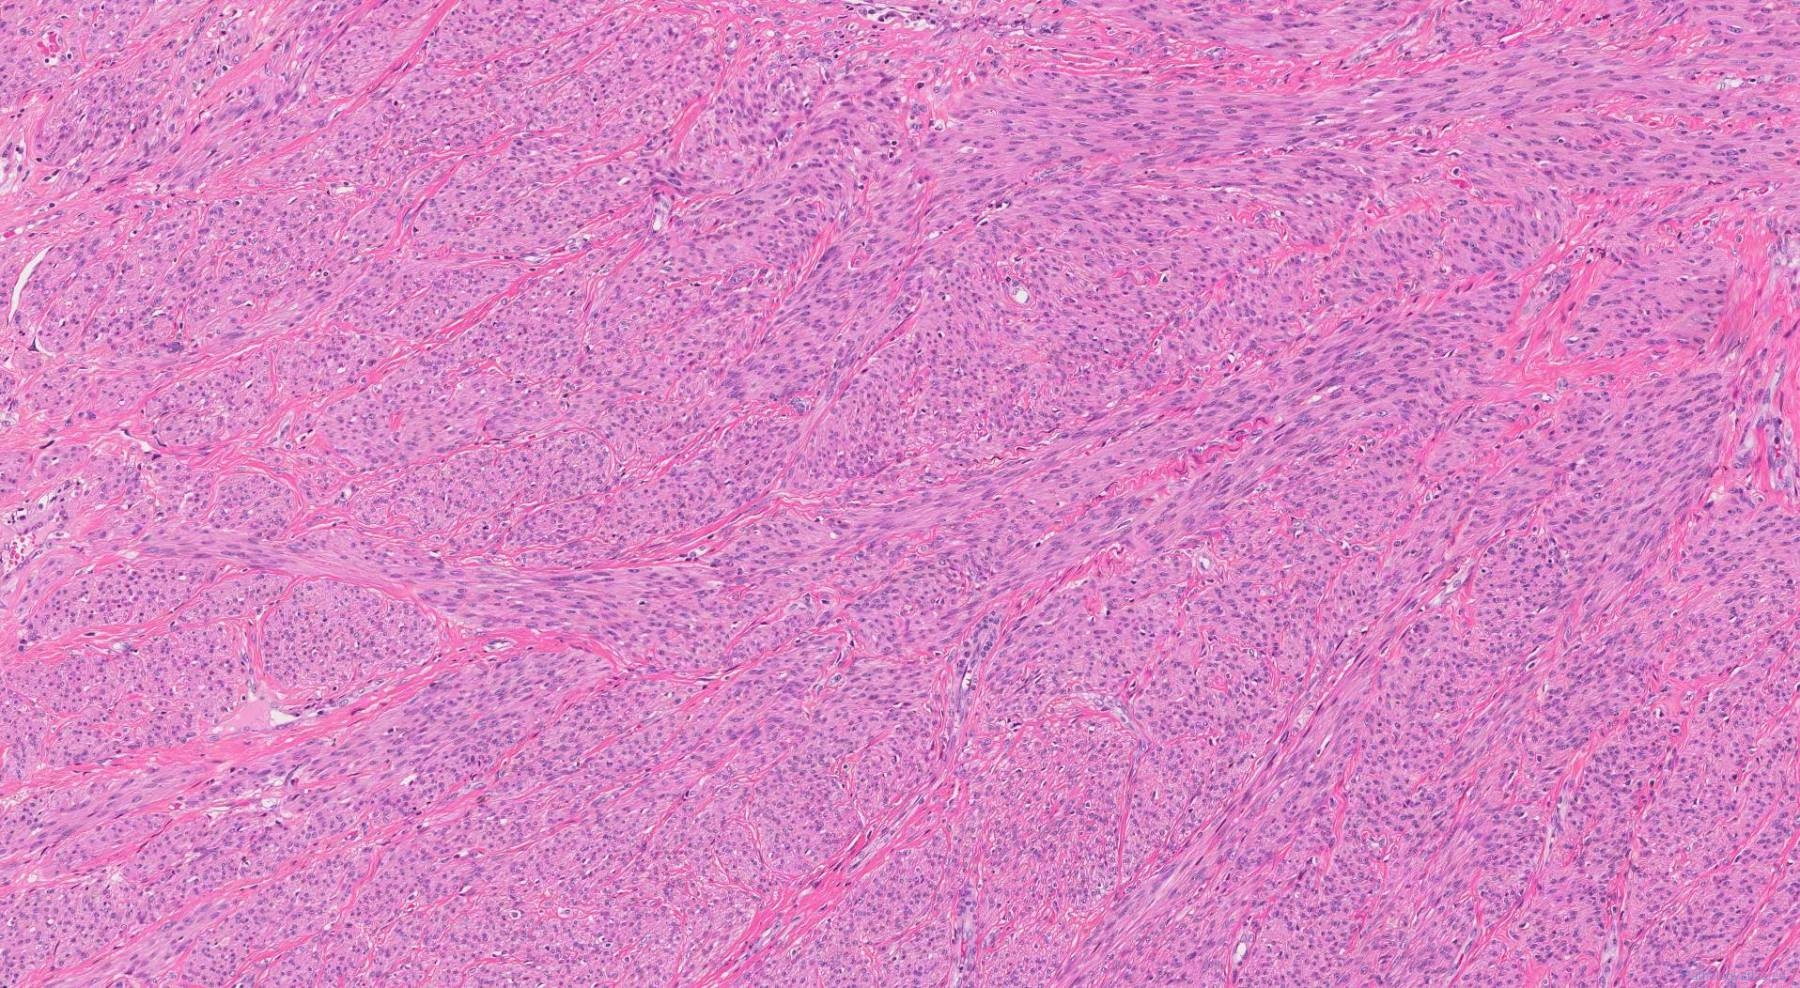

Leiomyoma Of The Uterus | Ottawa Atlas Of Pathology

www.pathologyatlas.ca

www.pathologyatlas.ca

Leiomyoma (Uterus) – BosnianPathology

www.bosnianpathology.org

www.bosnianpathology.org